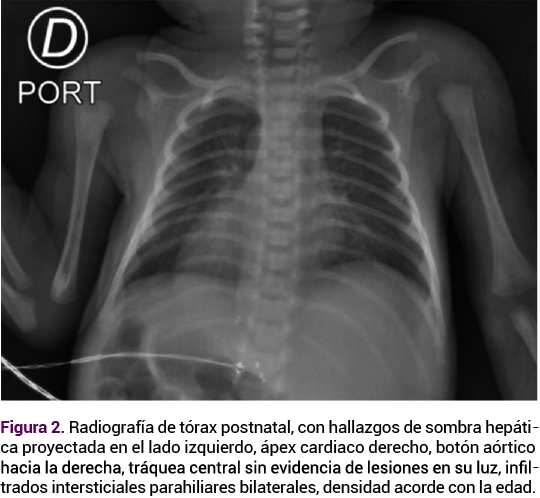

Debido a las altas tasas de complicaciones en los embarazos gemelares se indicó un control ecográfico estricto. El Doppler fetoplacentario y la ecografía obstétrica de la semana 29 no mostraron alteraciones hemodinámicas; sin embargo, en el feto B se observó un ápex cardiaco y estómago de lado derecho (Figura 1), hallazgos sugerentes de situs inversus totalis. En el feto A no se documentaron alteraciones de lateralidad, ni otras malformaciones anatómicas asociadas.

<strong>Figura 1</strong>

Figura 1.